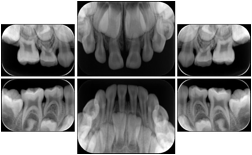

Intra-oral radiography typically involves acquisition of multiple images of various parts of the dentition. Many digital radiographic systems offer customized templates that are used for displaying the images in a study on the screen. These templates may also be referred to as mounts or view sets. The Structured Display Object represents a standard method of encoding and exchanging the layout and intended display of Structured Displays. A structured display object created in this manner could be stored with a study and exchanged with images to allow for complete reproduction of the original exam.

1. A patient visits a General Dentist where a Full Mouth Series Exam with 18 images is acquired. The dentist observes severe bone loss and refers the patient to a Periodontist. The 18 images from the Full Mouth Series along with a Structured Display are copied to a DICOM Interchange CD and sent with the patient to see the specialist. The Periodontist uses the CD to open the exam in his Dental Radiographic Software and consults via phone with the General Dentist. Both are able to observe the same exam showing the images on each user's display using the exact same layout.

Intra-oral Full Mouth Series Structured Display

Figure OO-1. Intra-oral Full Mouth Series Structured Display